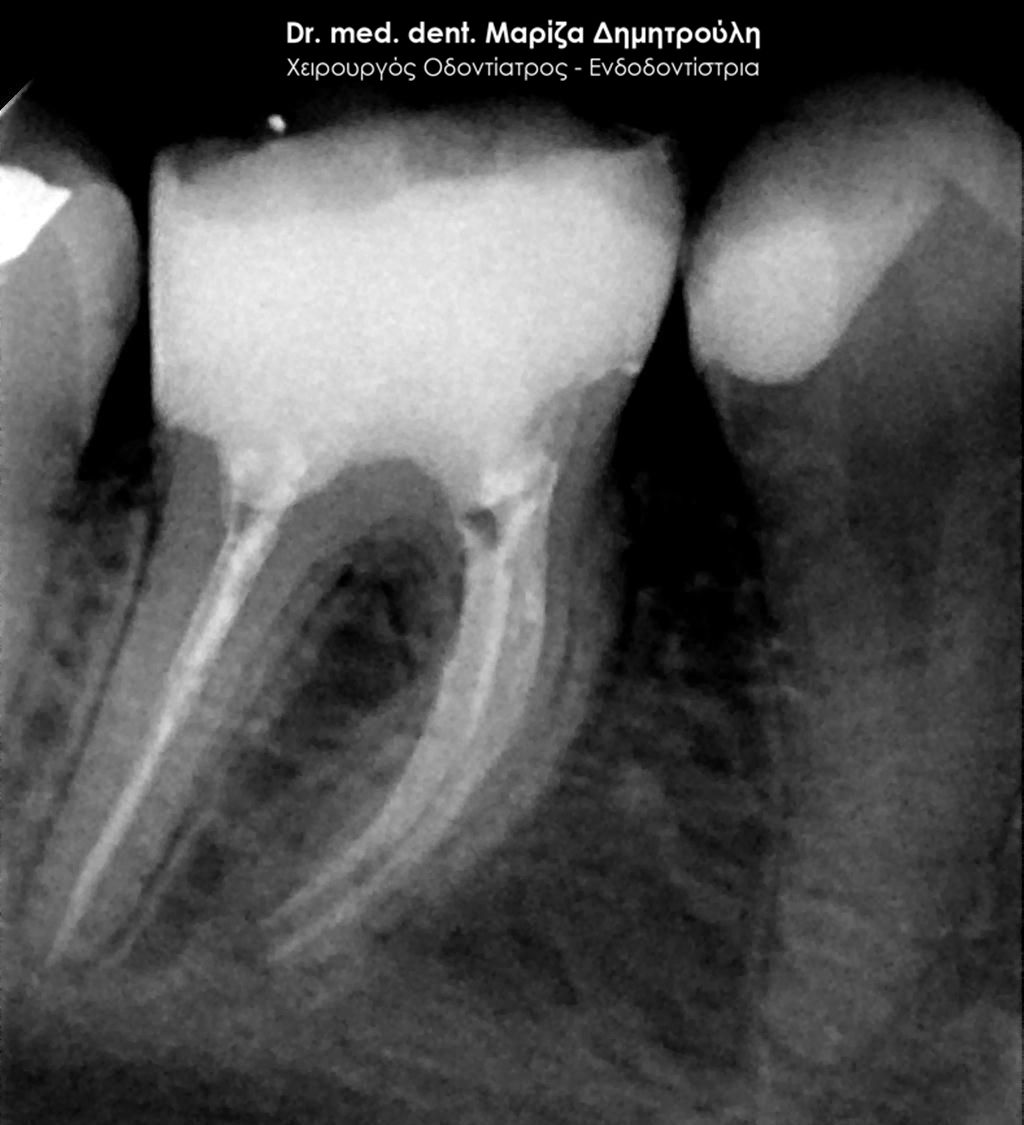

Η ασθενής περιγράφει έναν έντονο συνεχόμενο πόνο στη δεξιά πλευρά της άνω γνάθου που δεν την αφήνει τις τελευταίες μέρες μα εργαστεί. Μετά την κλινική και ακτινογραφική εξέταση της περιοχής διαπιστώθηκε οτι το υπαίτιο δόντι για την πρόκληση των έντονων συμπτωμάτων ήταν ο δεύτερος δεξιός άνω γομφίος, ο οποίος διέθετε ένα παλιό βαθύ σφράγισμα που πίεζε το νεύρο του δοντιού.

Μετά τη χορήγηση τοπικής αναισθησίας αφαιρέθηκε το παλιό σφράγισμα και εντοπίστηκαν οι ριζικοί σωλήνες του δοντιού (βλέπε φωτογραφία). Μετά την κατάλληλη επεξεργασία των ριζικών σωλήνων και εφόσον το δόντι ήταν ασυμπτωματικό η απονεύρωση ολοκληρώθηκε με την έμφραξη των ριζικών σωλήνων με ειδικό εμφρακτικό υλικό.

ΠΡΙΝ

ΜΕΤΑ